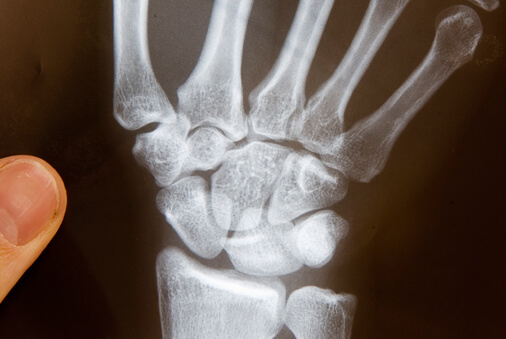

Gern möchte ich mich Ihnen vorstellen: als staatl. anerkannter Ergotherapeut mit Aus- und Weiterbildungen im Bereich Handrehabilitation/Chirurgie bin ich spezialisiert auf Handtherapie und Handrehabilitation. Meine Mitarbeiter der Praxis für Ergotherapie in Bochum und ich verfügen über mehrjährige Berufserfahrung und den entsprechenden zertifizierten Qualifikationen. Wir stehen seit 18 Jahren für Qualität und Kompetenz in der Ergotherapie in Bochum.

Leistungen der Praxis für Ergotherapie und Handrehabilitation

Das Leistungsspektrum der Praxis für Ergotherapie und Handrehabilitation umfasst Behandlungen aus folgenden Bereichen: